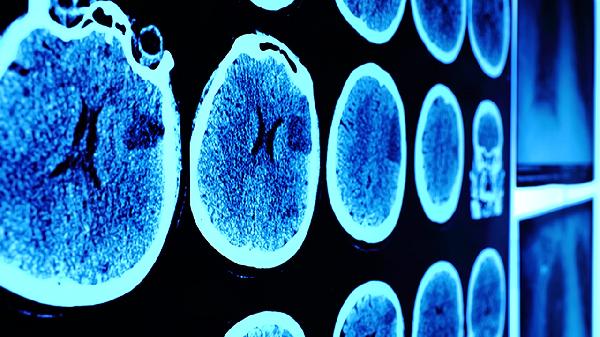

伤后1周、1个月需神经外科随访,必要时进行CT或MRI检查评估恢复情况。学生及运动员恢复学习训练前需经专业评估。遗留注意力不集中等症状时,应接受认知功能康复训练。